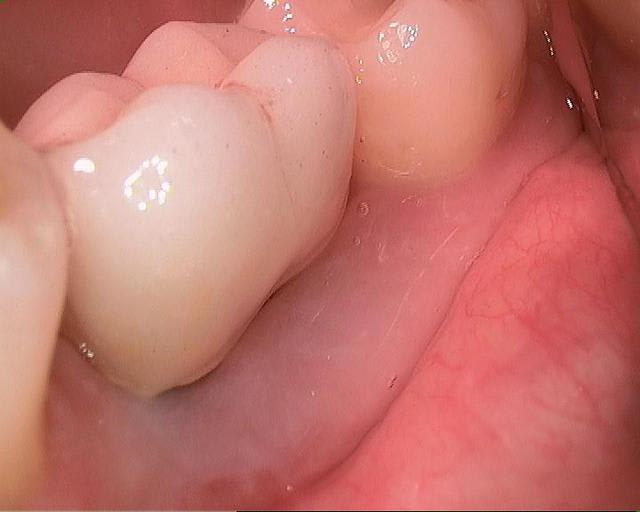

Et une mandibule en MCI cet aprés midi. Comme tu vois ça ne saigne pas beaucoup.